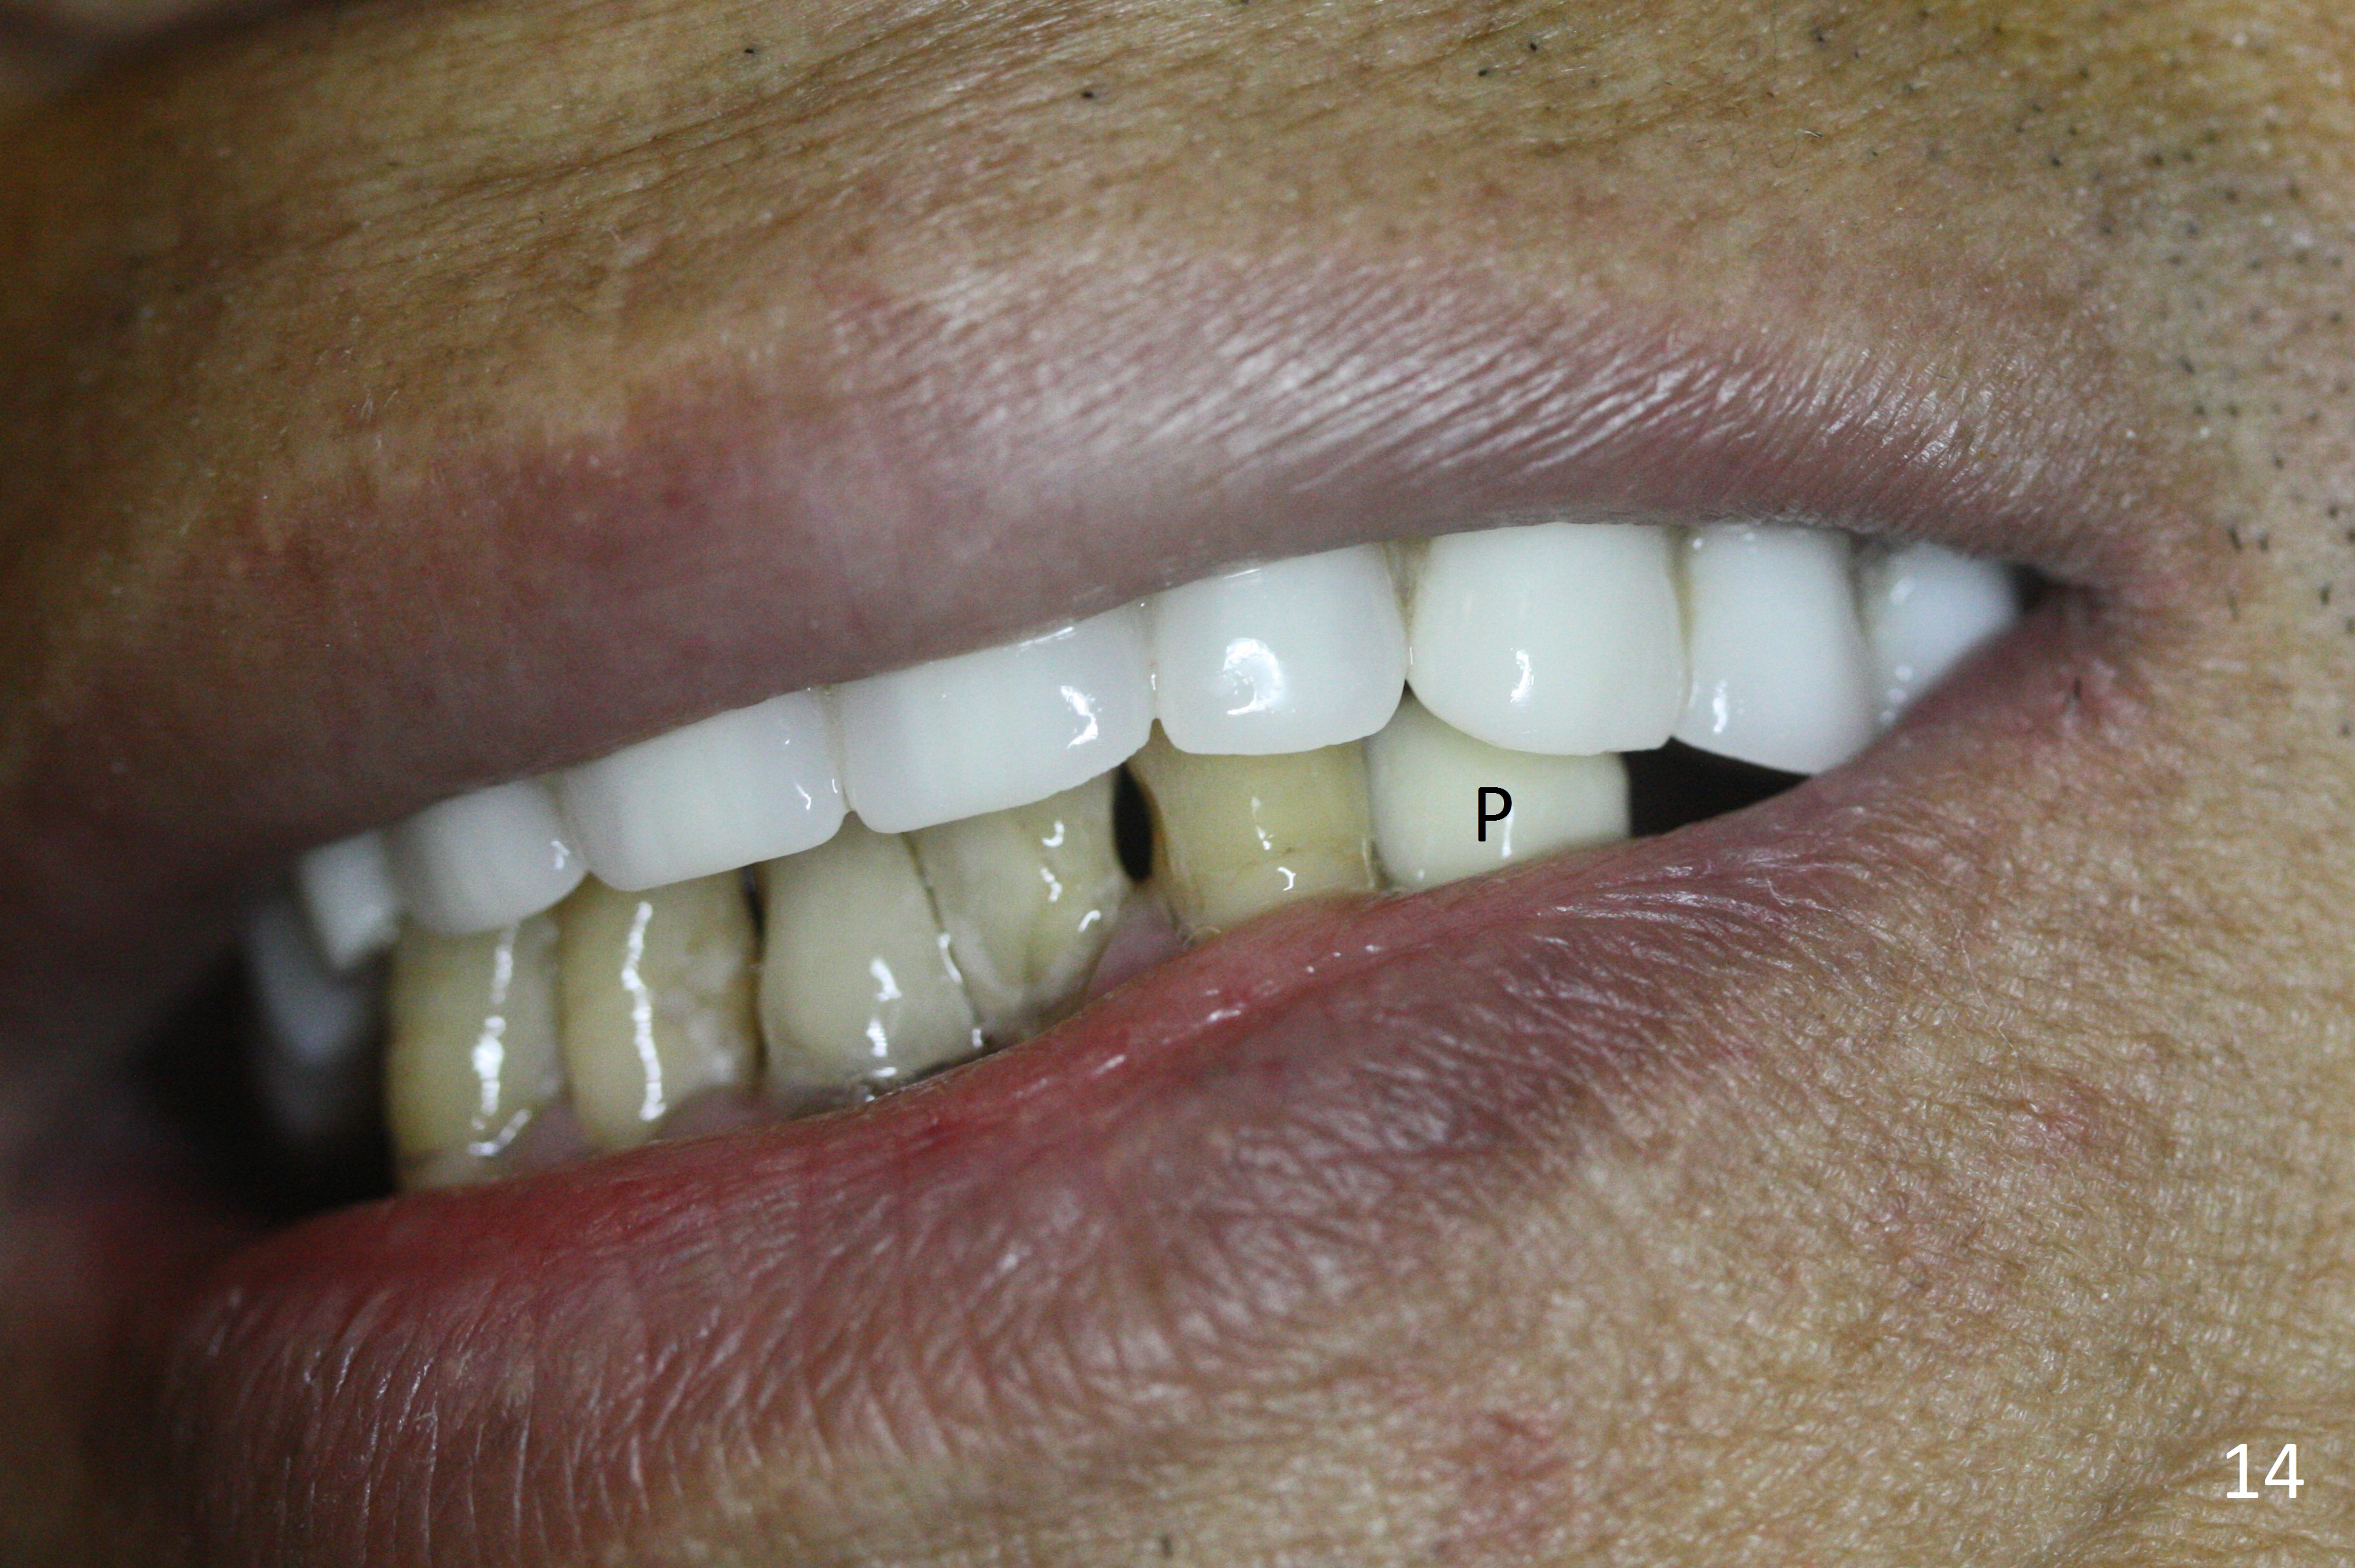

The patient returns 2 days postop because of hemorrhage (Fig.10,11 * after removal of loose periodontal dressing). Periodontal dressing is repacked (Fig.12). The hemorrhage may be due to incomplete removal of granulation tissue or invasion of the Incisive vessel intraoperatively, although there is no pain or paresthesia postop. Soft food is recommended without the upper complete denture. A provisional is fabricated (Fig.14 P) nearly 3 months postop (after changing the 5.5x5(5) mm abutment to 4.5x5(4) mm, Fig.13) when an implant is being place is #31.